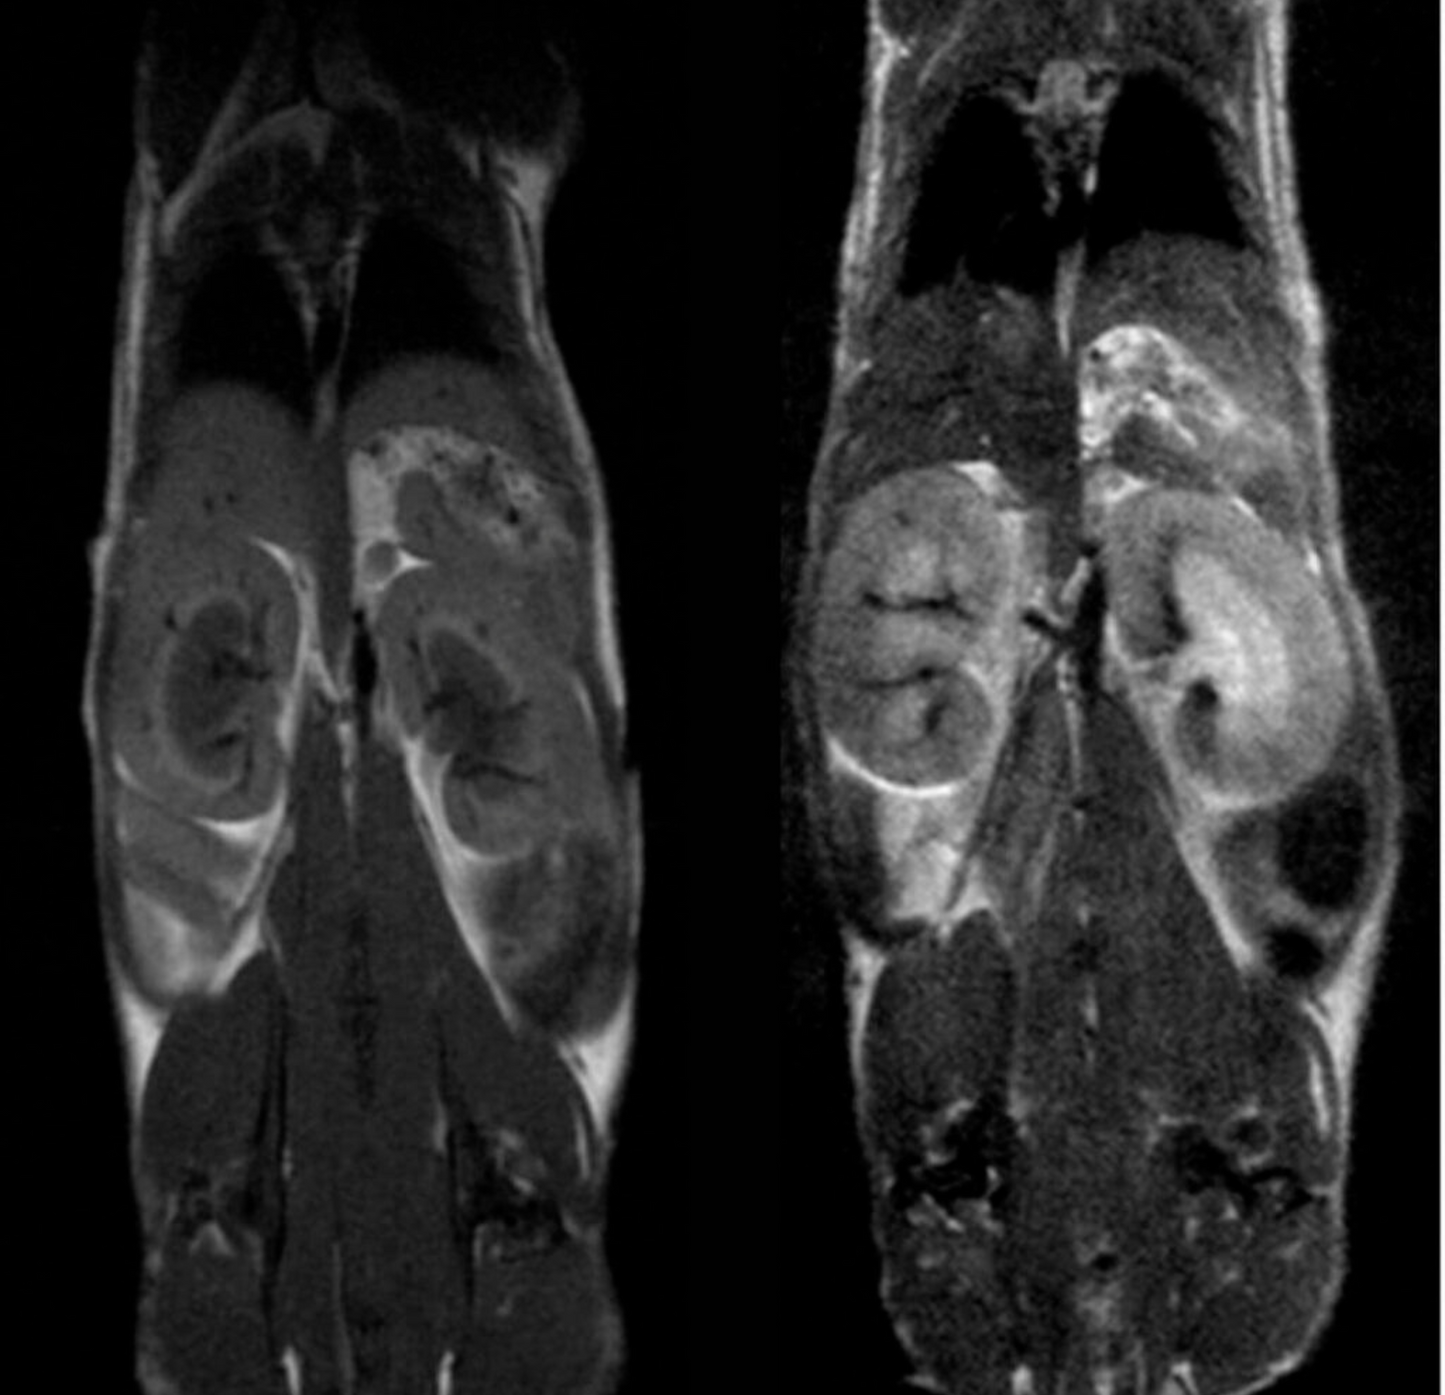

High Performance Preclinical Magnetic Resonance Imaging (MRI) Mice Only

The M-Series™ systems are cryogen/cooling-free, self-shielded, high-performance MRI systems based on permanent magnet technology. The M-Series systems allow preclinical researchers, with or without in-depth knowledge of MR physics, to utilize the gold standard method in soft tissue imaging without the cost, complexity, and technical burden of superconducting MRI systems. Varying-sized models allow for imaging of mice, rats, similarly sized species/samples, as well as brains of non-human primates. Based on the permanent magnet technology, there are no special infrastructure requirements, operating and maintenance costs are minimal, and they can be easily integrated into existing lab space. These 1 Tesla systems are optimized for anatomical, functional, and molecular imaging applications in cancer, cardiac, neuroscience, and multimodal imaging. The optional SimPET insert can be integrated with the M-Series for simultaneous PET/MRI acquisition.